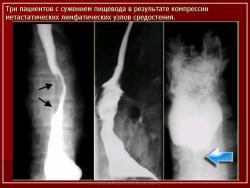

Лимфогранулематоз.

Приложения:

1.L.Slayd53.JPG2.L.Slayd54.JPG3.L.Slayd55.JPG4.L.Slayd56.JPG5.L.Slayd57.JPG